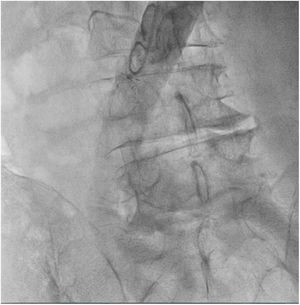

El paciente se traslada a la sala de hemodinamia donde se intenta la extracción del dispositivo. Se utilizan diferentes catéteres lazo de 10, 25 y 30 mm, así como lazos de fabricación con guías largas y cortas intentando movilizar el dispositivo desde diferentes accesos vasculares (acceso bifemoral 6 y 18 Fr y radial 6 Fr) (figuras de la 1 a la 4). Se produce como complicación disección de aorta abdominal con extensión a arteria ilíaca común derecha (figuras 5 y 6) y pérdida total del flujo en extremidad inferior ipsilateral con signos y síntomas de isquemia arterial aguda, por lo que el paciente es trasladado de forma urgente al quirófano de angiología y cirugía vascular. Se realiza disección de aorta abdominal infrarrenal vía laparotomía media con aortotomía longitudinal en el lugar de la localización del cuerpo extraño visualizándose el dispositivo migrado anclado a la íntima-media de la pared arterial. Se procede a su extracción y posteriormente se realiza cierre de aortotomía con parche de pericardio bovino fijando la disección y corrigiendo así el defecto (figuras de la 7 a la 9). El paciente sale de quirófano con pulso pedio bilateral y excelente perfusión distal.